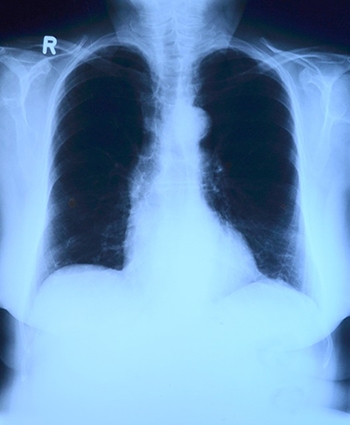

여성이 폐암 수술 후 생존율 높아

새로운 연구에 따르면 여성은 남성보다 폐암 수술 후 생존율이 더 높은 것으로 나타났다.